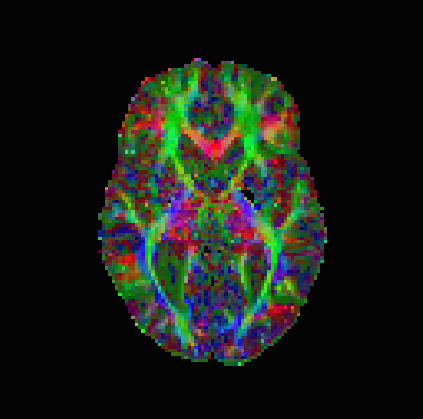

The results are in Table 2 and Figures 6–8, again with the first of the figures showing the colour-coded principal eigenvector of the reconstruction, the second showing the fractional anisotropy and principal eigenvectors, and the last one the errors in the latter two, in a colour-coded manner. Again, all plots are masked to represent only the non-zero region. In the figures, we concentrate on error bounds based on 95% confidence intervals, as the results for the 90% and 99% cases do not differ significantly according to Table 2.

This time, the linear approach (3.3) has best overall reconstruction (Frobenius PSNR), while the nonlinear approach (3.2) has clearly the best principal eigenvector angle reconstruction besides the regression, which does not seem entirely reliable regarding our regression-based pseudo-ground-truth. The constraints based approach (3.5), with 95% confidence intervals is, however, not far behind in terms of numbers. More detailed study of the corpus callosum in Figure 8 (small picture in picture) and Figure 7 however indicates a better reconstruction of this important region by the nonlinear approach. The constrained approach has some very short vectors there in the white region. Naturally, however, these results on the in vivo data should be taken with a grain of salt, as we have only a somewhat unreliable pseudo-ground-truth available for comparison purposes.